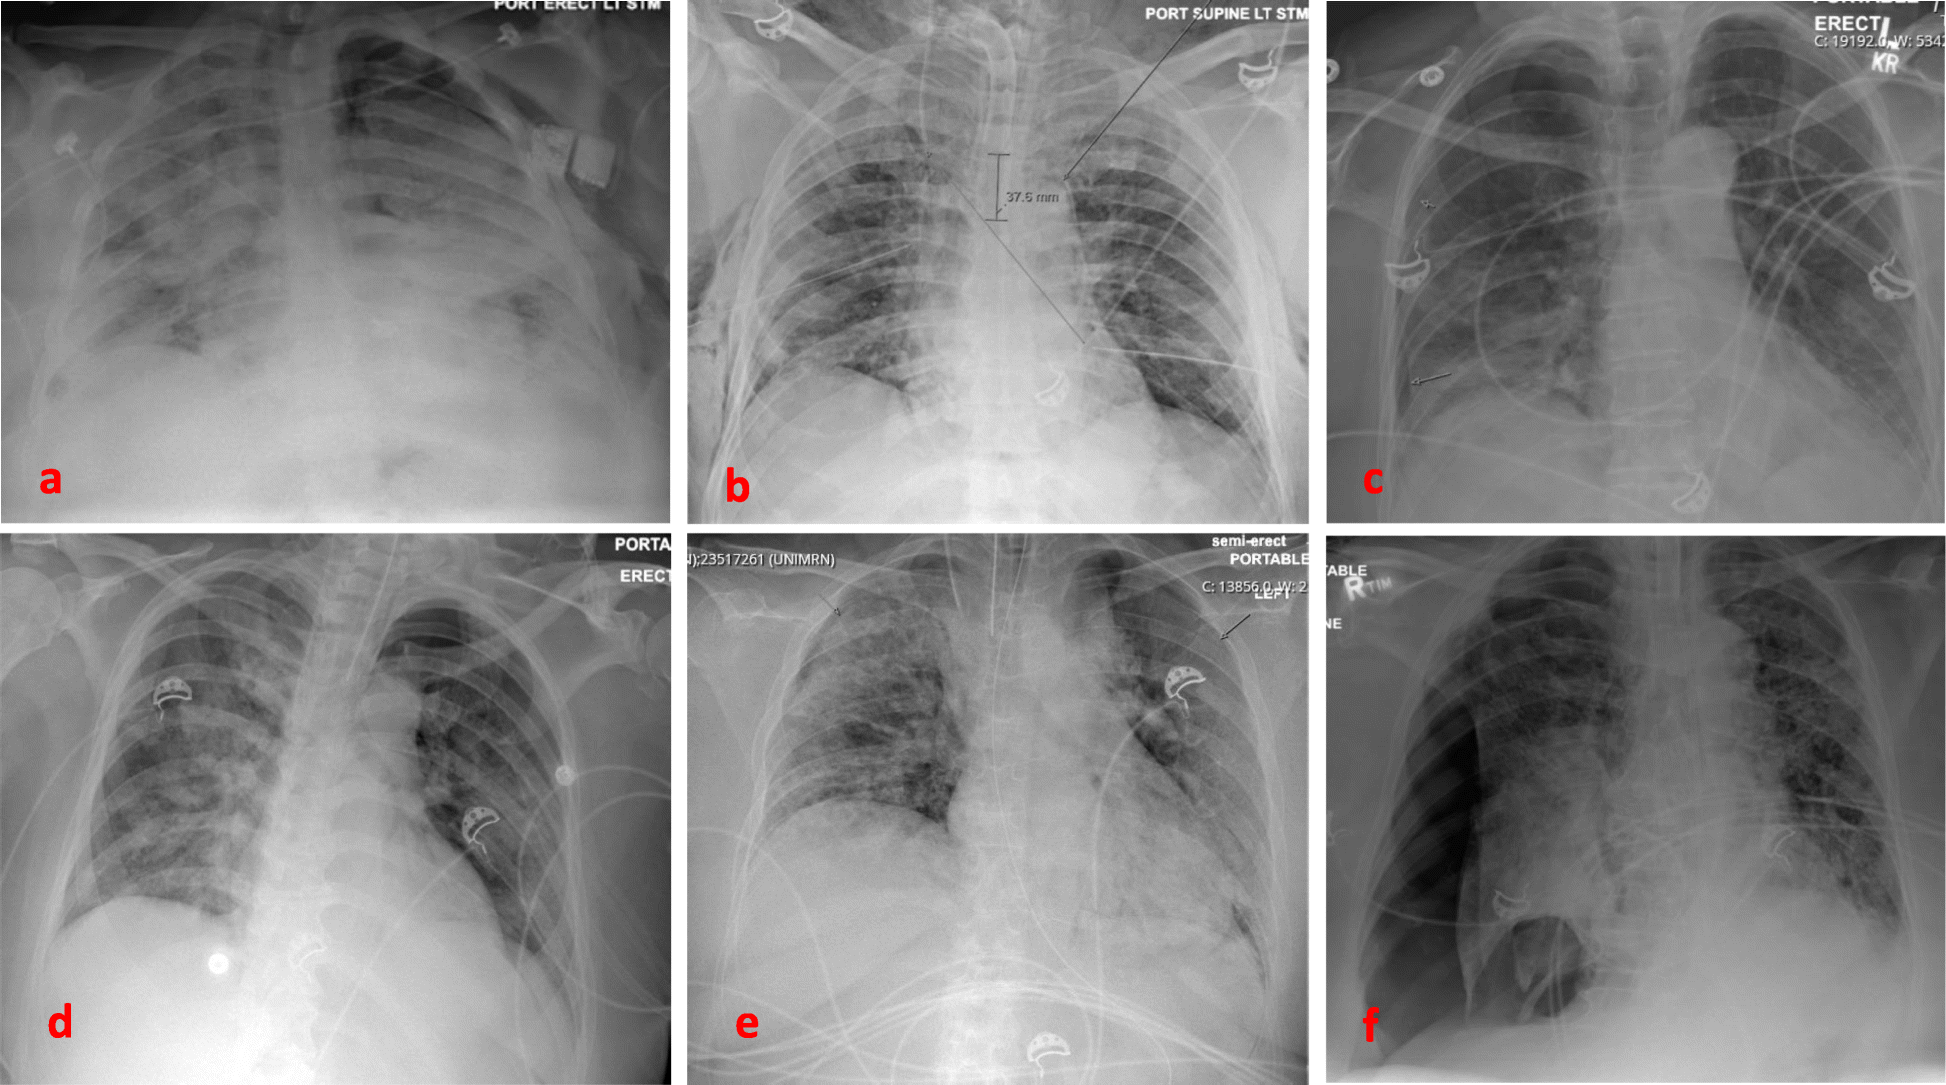

Fig. 3

From: Pneumothorax in COVID-19 disease- incidence and clinical characteristics

Chest radiograph for each patient revealing the pneumothorax. From top left: a Case-1 Large, left. b Case − 2 after pneumothoraces developed and chest tubes were placed. Residual right sided subcutaneous emphysema. c Case − 3. Moderate, right. d Case-4. Small, left apical e Case-5. Small, bilateral f Case- 6. Large, right